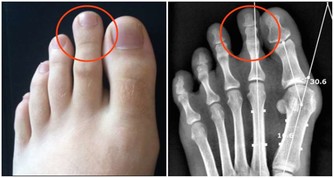

初次就診時,小董不僅黑眼圈嚴重,精神不振,還有易疲勞、睡覺打呼嚕等症狀。

小孩擠眉弄眼,有黑眼圈家長要引起重視

小朋友因為好動,日常會有很多小動作,很多家長會不以為然,但如果發現寶寶長期以往臉部有奇怪的表情,那就要引起注意了,寶寶很可能是患上過敏性鼻炎了。

以下症狀,如果出現其中一個症狀,家長都應注意觀察或到專業醫院諮詢,做好兒童過敏性鼻炎的預防工作:

1.一到春季或秋季,頻繁的打噴嚏流鼻涕

2.黑眼圈大而重

3.夜裡睡覺時張口呼吸打呼嚕

4.習慣性揉鼻子、揉眼睛、擠眉弄眼

5.容易出現皮膚瘙癢